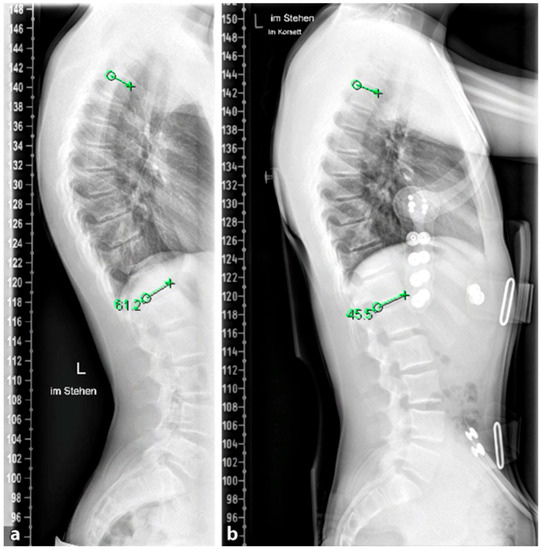

To avoid the regular surgical lengthening procedure, MCGRs were developed and approved for the treatment of EOS in Europe in 2009. MCGRs are telescopically extendable distraction rods. They can be distracted non-invasively, on an outpatient basis, by externally magnetically controlled lengthening using electromagnets. Figure 5 illustrates the progression of treatment for a patient with AIS, starting from initial diagnosis, through the bending radiographs, to the postoperative phase with implanted MCGR, and finally, the maintenance phase involving spondylodesis.

Figure 5. (a,b). Initial radiographs of a patient with adolescent idiopathic scoliosis. (c,d). Bending radiographs. (e,f). Postoperative image displaying implanted magnetically controlled growing rods as a dual rod system. (g,h). The patient was treated with a spondylodesis upon the completion of growth to maintain correction success (Reprinted with permission [10]).